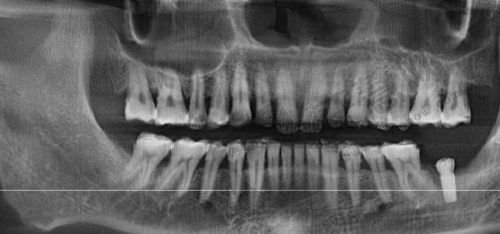

南宁同步口腔穿颧骨种植术 74200 元起项目专为上颌骨重度吸收患者定制。正常情况下,上颌骨骨量重度不足时传统种植牙手术难以进行,而穿颧骨种植术突破了这一限制。手术通过将种植体植入颧骨,利用颧骨骨量支撑种植体实现牙齿种植。南宁同步口腔开展此手术会采用精良设备和技术,确保精细性和安心性。术前,医生会对患者进行全方面口腔检查,包括口腔 CT 等,了解口腔状况和骨骼结构,制定个性化治疗方案。手术中,医生凭借丰富经验和不错技术将种植体正确植入颧骨。术后,医院提供专精护理指导帮助患者修复。74200 元起的收费包含手术费、种植体费用等,但具体价格会因种植体品牌、手术复杂程度等因素不同。

南宁同步口腔穿颧骨种植术 74200 元起有诸多优势。技术优势,医院采用精良设备和技术,术前用口腔 CT 等设备详细检查患者口腔状况,为手术提供精细数据。手术中医生凭借经验和技术正确植入种植体,提高成功几率。价格优势,相较于市场上其他医院穿颧穿翼种植牙价格,74200 元起收费更亲民,虽价格受多种因素影响,但总体为患者节省费用。服务优势,术前医生与患者充分沟通,了解需求和期望,制定个性化方案。术后提供专精护理指导,帮助患者修复。南宁同步口腔在本地口碑良好,患者可放心选择。医院还会定期回访患者,了解修复情况,解决问题。